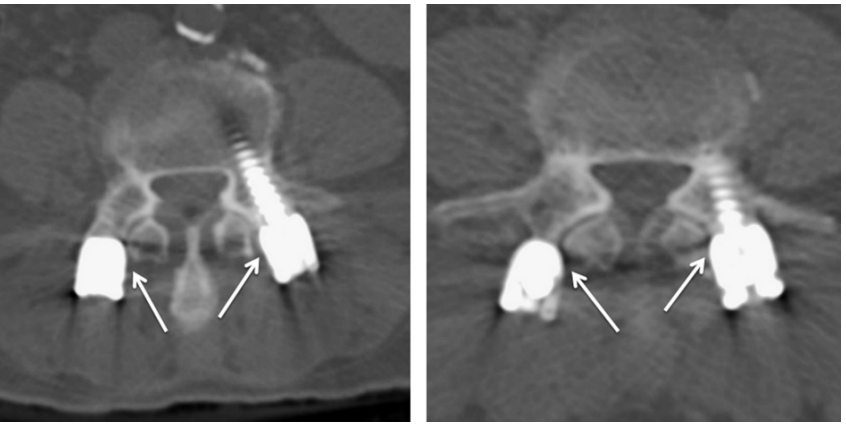

对于椎弓根螺钉损伤关节突关节的影像学评估,目前已有的临床研究主要依据内固定术后CT扫描观察螺丝、螺帽或连接杆对关节突关节的损伤程度。本期我们将已有的分级系统进行汇总,为大家术后评估和进一步研究提供参考。

2.Badu分级

0级:螺钉没有触及关节

1级:螺钉触及关节侧缘,但未进入关节腔内

2级:螺钉进入关节腔内,但进入距离<1 mm(右)

3级:螺钉进入关节腔内,进入距离≥1 mm

左侧1级,右侧2级

左侧1级,右侧0级